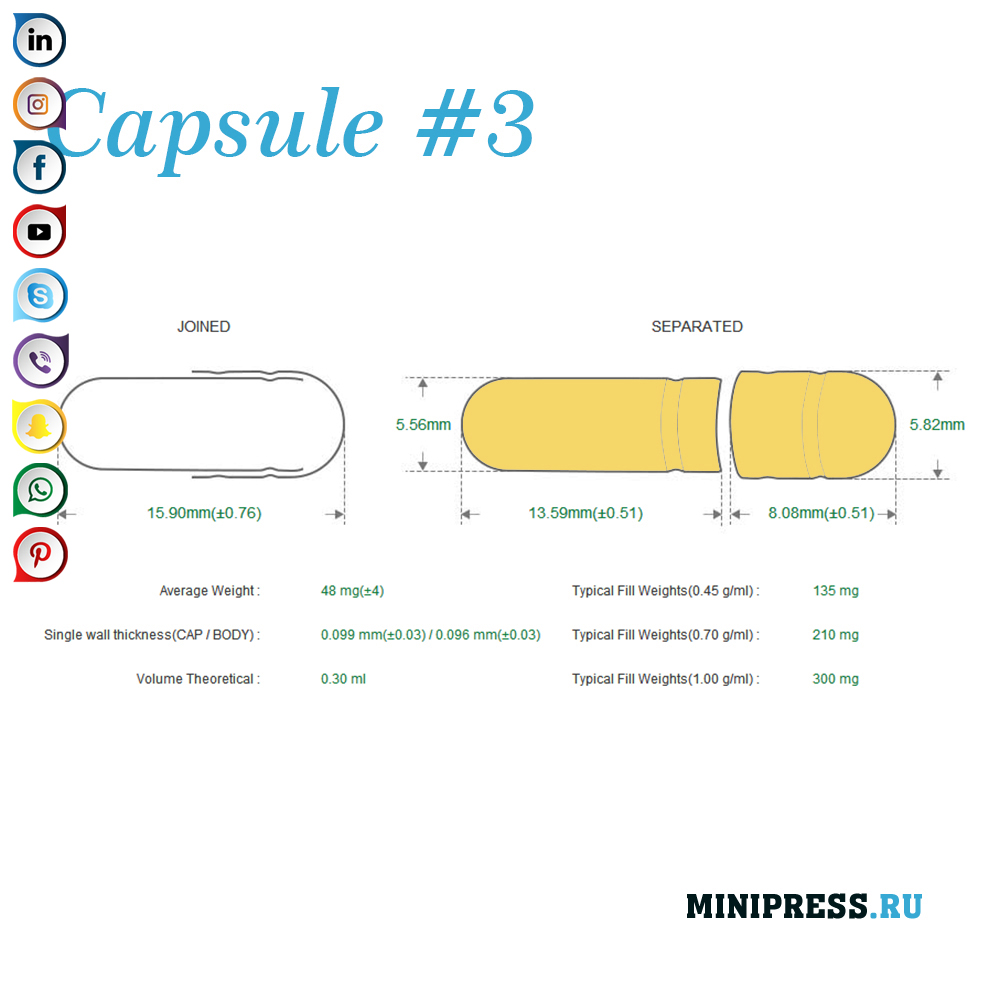

Velike zelatinskih kapsula: 000,00,0,1,2,3,4,5, A, B, C, D, E.